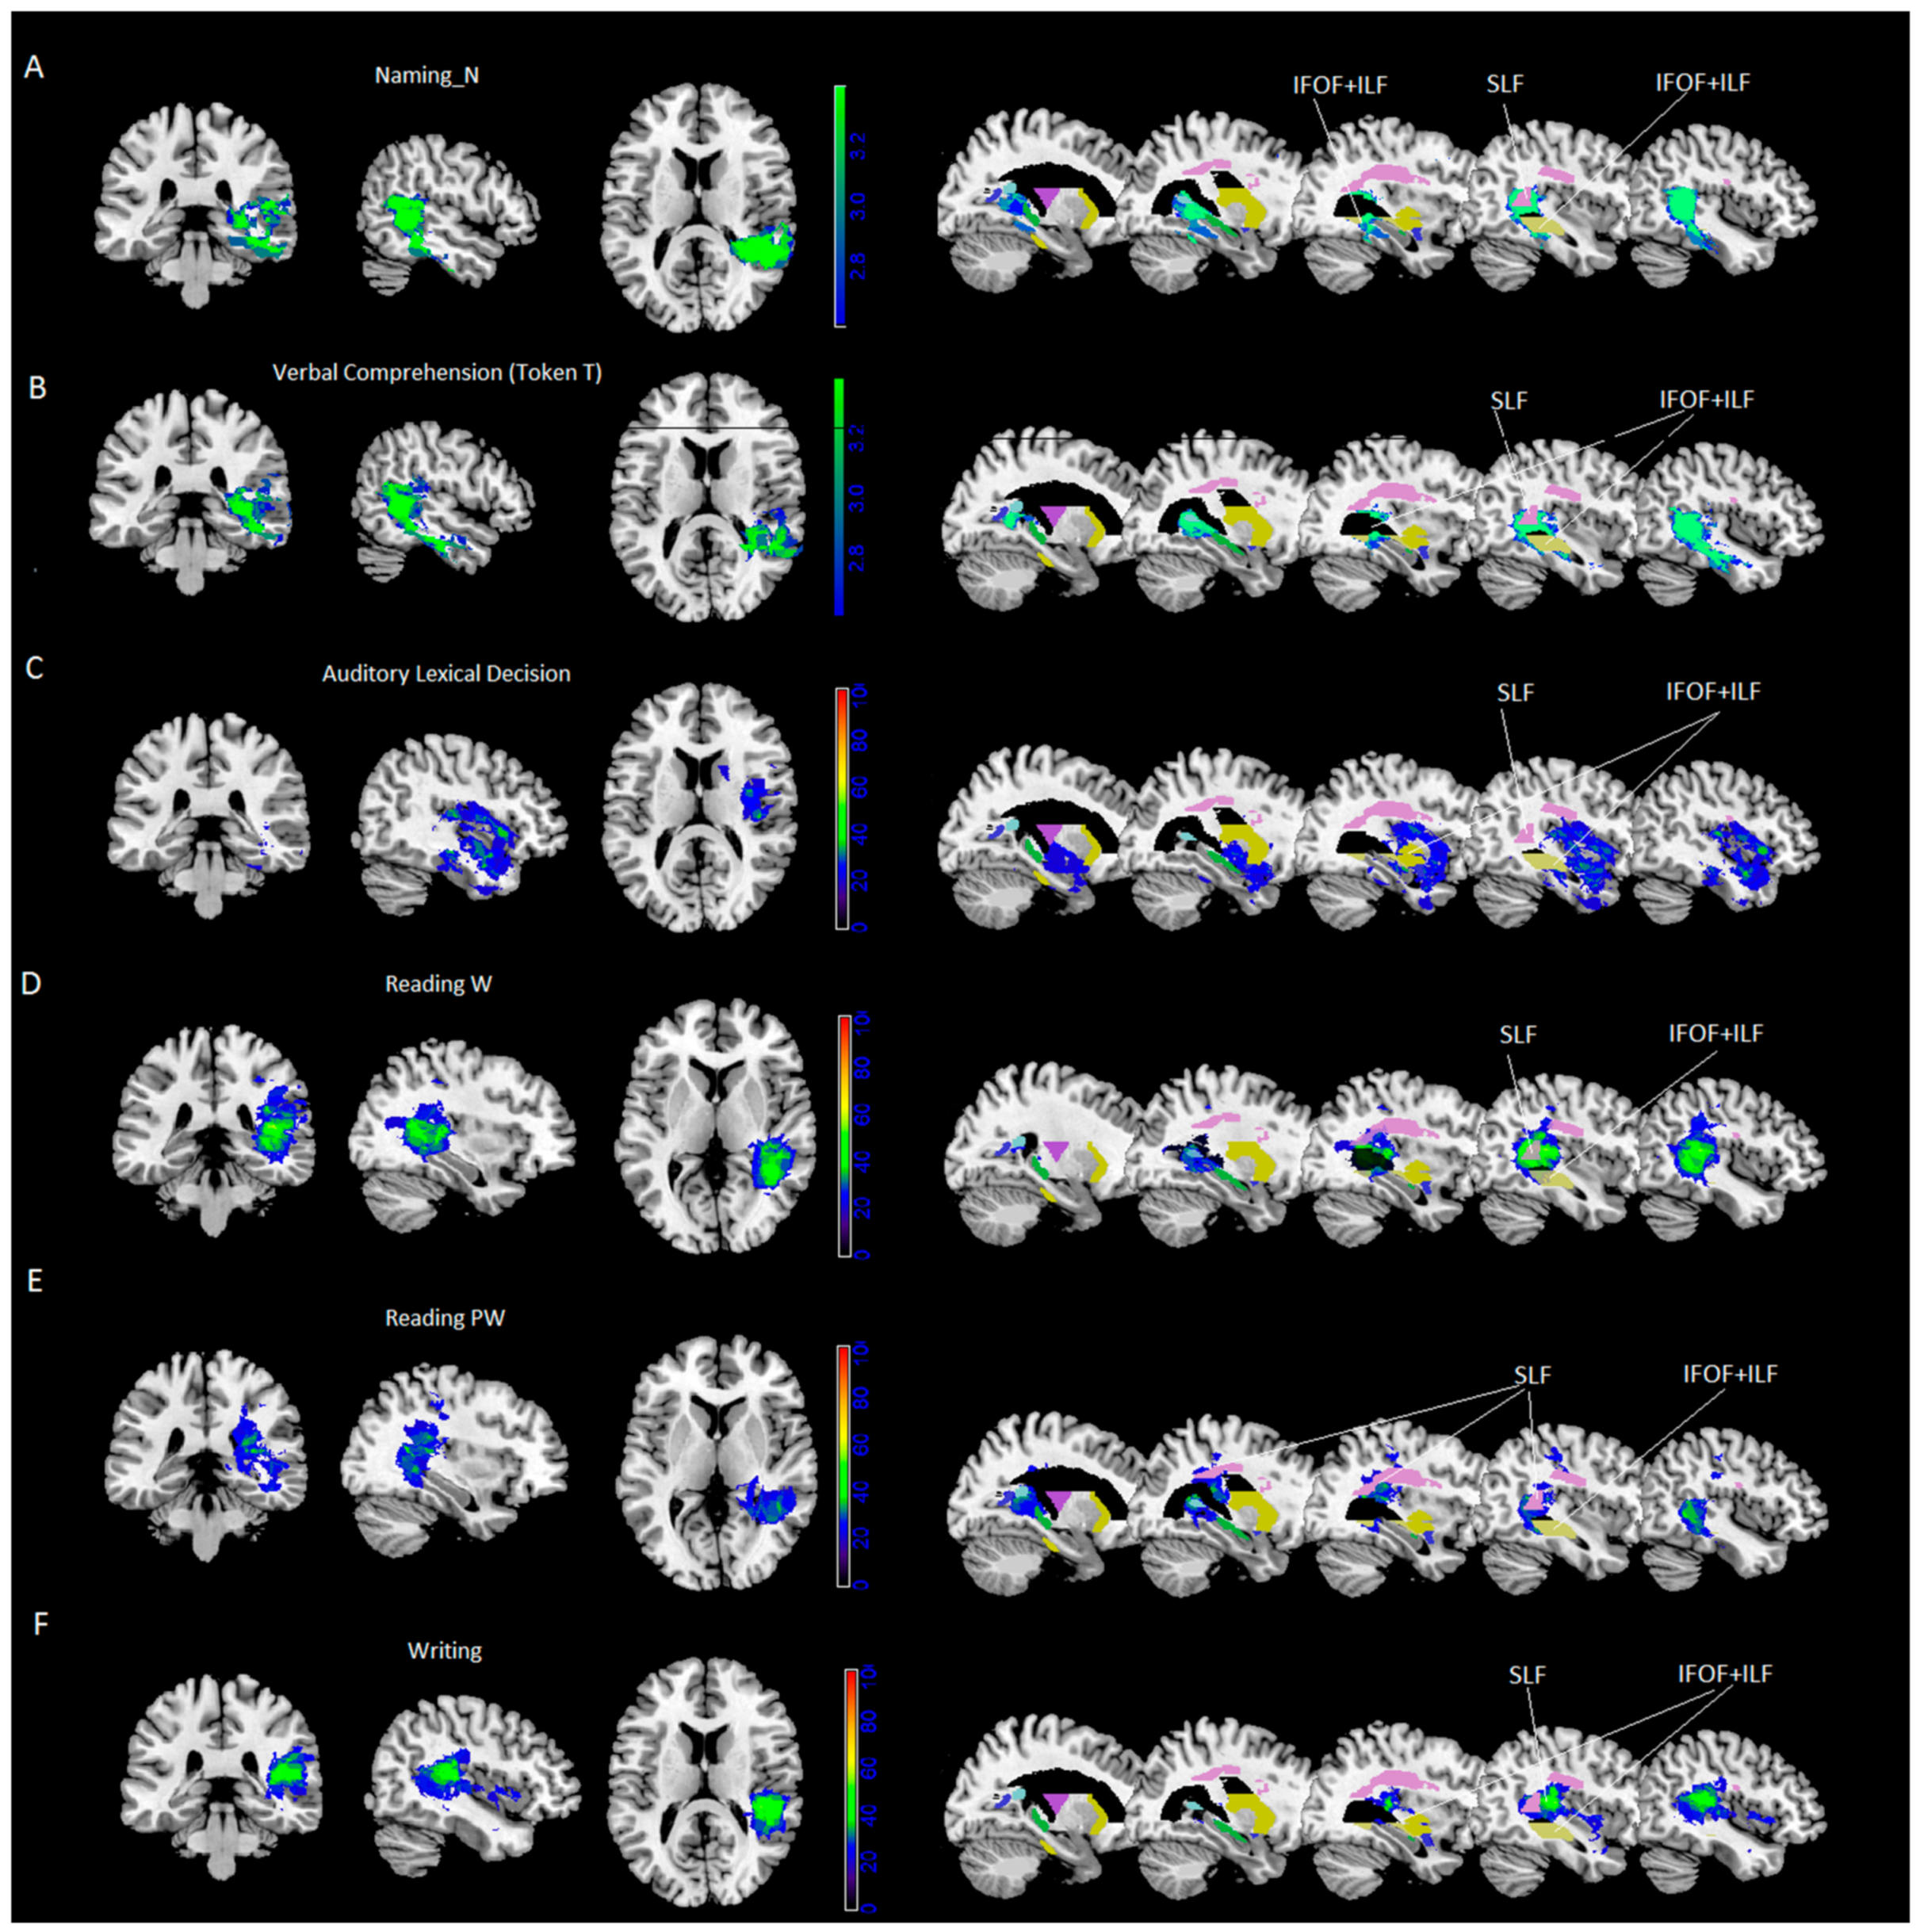

- Results of VLSM analyses were significant for noun naming and verbal comprehension (Token Test) only. VLSM performed for noun naming revealed 24% of the voxels damaged in the middle temporal cortex and, to a lesser extent (between 15% and 10%), in the inferior and superior temporal gyrus, the hippocampus/parahippocampal area and the fusiform gyrus (Figure 1A). In addition, at subcortical level we found portions of the posterior thalamic radiation and the sagittal stratum [including the inferior fronto-occipital fasciculus (IFOF) and the inferior longitudinal fasciculus (ILF)], with 40% of overlapping lesions, and to a lesser extent (% voxels damaged between 29% and 14%), the retrolenticular part of the internal capsule, the superior longitudinal fasciculus (SLF, with 50% of overlapping lesions) and pars of the tapetum (see Table 4 and Figure 1A).

- VLSM analyses performed for the Token Test revealed 26% of the voxels damaged in the middle temporal cortex and, to a lesser extent (between 15% and 10% of the voxel damaged), in the inferior and superior temporal gyrus, and the hippocampus (Figure 1B). At subcortical level we found parts of the sagittal stratum (including IFOF and ILF, with 43% of overlapping lesions), posterior corona radiate and posterior thalamic radiation and the retrolenticular part of the internal capsule, pars of the tapetum and, to a lesser extent (% voxels damaged between 26% and 5%), the superior longitudinal fasciculus (SLF, with 49% of overlapping lesions) and pars of the splenium (see Table 4 and Figure 1B).